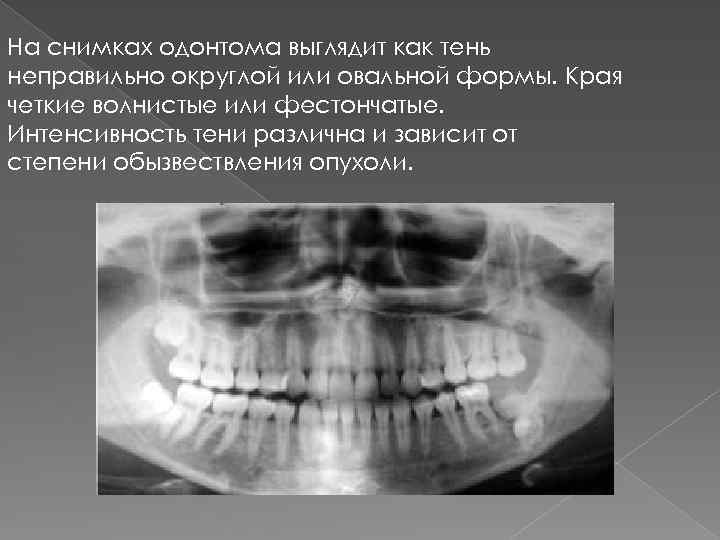

Одонтома нижней челюсти: фотографии и медицинская информация